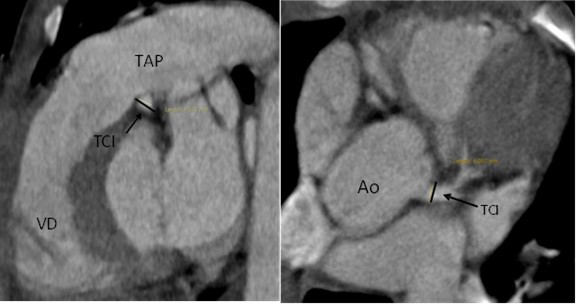

La angiotomografía coronaria demostró un origen anómalo de la arteria coronaria derecha a partir del seno coronario izquierdo, con trayecto interarterial entre la aorta y el tronco de la arteria pulmonar, asociado a una reducción aproximada del 50% del calibre en su segmento proximal (Fig. 1). Adicionalmente se observó leve dilatación difusa del tronco coronario izquierdo y del segmento proximal de la arteria circunfleja, sin evidencia de aneurismas ni estenosis en los segmentos medio y distal (Figs. 2 y 3).

Figura 2. Medición axial del tronco coronario izquierdo (TCI) que muestra origen y trayecto habitual, dilatación difusa del segmento proximal distal, sin zonas de estenosis. TAP: tronco de arteria pulmonar.